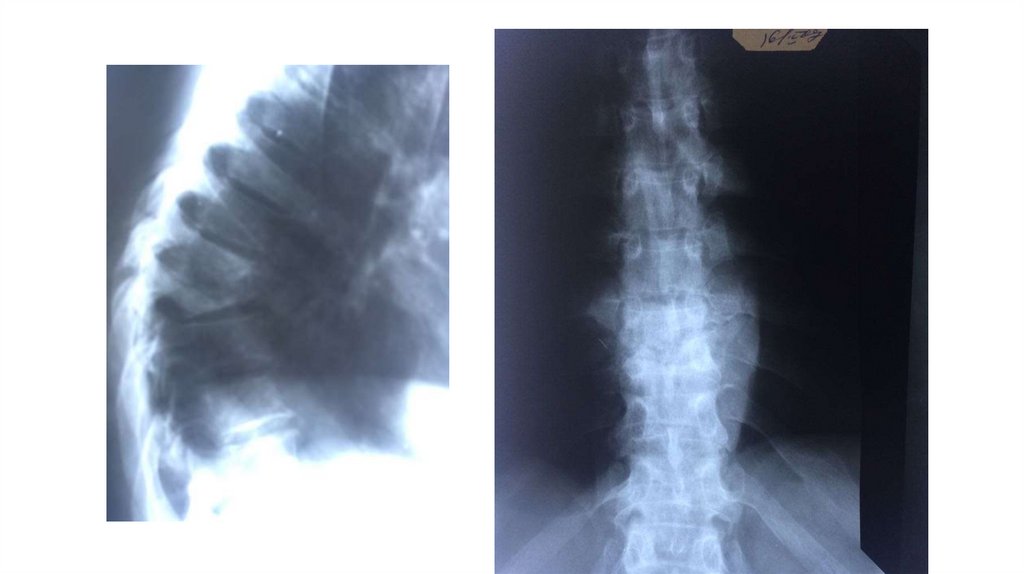

Воспалительные заболевания опорнодвигательного аппарата

«Воспалительные

заболевания опорнодвигательного аппарата»